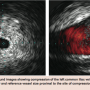

Access was then obtained in the right femoral vein to position a catheter at the inferior vena cava-common iliac vein bifurcation to accurately position the left common iliac vein stent. However, selective venography of the right femoral vein revealed compression of the right common iliac vein (Figure 3) at the level of a calcified nodule adjacent to the vein that was suspicious of arterial calcification. Access was then obtained in the right common femoral artery to further evaluate this finding.